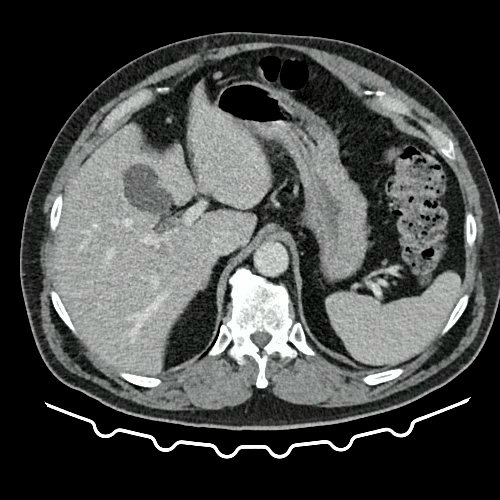

• TAC de tórax con contraste EV (Día 10): La porción visualizada de la glándula tiroides es de características normales. Las estructuras vasculares supraaórticas son de características normales, permeables. La aorta ascendente, el cayado y la aorta descendente son de calibre y trayecto conservados, permeables. Las estructuras venosas mediastinales: vena cava superior, vena cava inferior, venas pulmonares superiores e inferiores y venas ácigo-hemiácigos, son de calibre y trayecto conservado, permeables. Vena ácigos prominente. La arteria pulmonar y sus ramas son de calibre y trayecto conservados, permeables. Relación aórtico-pulmonar conservada. El corazón es de tamaño normal. El pericardio es de espesor conservado. El esófago es de calibre y trayecto normales. El mediastino está en posición central. No se observan adenomegalias mediastinales, axilares o hiliares. El árbol traqueobronquial no presenta alteraciones. Aisladas atelectasias laminares en ambos lóbulos inferiores y en segmento lingular inferior. No se observa engrosamiento o derrame pleural. Marcados cambios osteoartrósicos de la columna dorsal.

• TAC de abdomen y pelvis con contraste EV (Día 10): El hígado es de forma, tamaño y situación habituales. Su superficie es lisa, y sus bordes son agudos. No presenta alteraciones densitométricas ni efectos de masa focales. La vía biliar intra y extrahepática es de calibre conservado. La vesícula biliar es de forma, tamaño y situación normales, sin imágenes que sugieran la presencia de litiasis. Tener en cuenta que este método puede pasar por alto litiasis colesterínicas. El bazo es de forma, tamaño y situación normales. El eje esplenoportal es de calibre y trayecto conservado. El páncreas es de características normales. El conducto de Wirsung es de calibre conservado. Las glándulas adrenales son normales. Ambos riñones son de forma, tamaño y situación habituales. Sin evidencia de alteraciones calicopiélicas ni ureterales. Quistes simples corticales en riñón izquierdo, el mayor de ellos en polo superior, que mide 16 mm. Discreta reticulación de la grasa perirrenal bilateral. La aorta, las arterias ilíacas primitivas, internas, externas y femorales, son de calibre y trayecto conservado. La vena cava inferior y las venas ilíacas primitivas, internas, externas y femorales son de calibre y trayecto conservados. Filtro de vena cava inferior infrayacente a venas renales. No se observan adenomegalias intraperitoneales, retroperitoneales, ilíacas ni inguinales. No se observan alteraciones a nivel del tracto gastrointestinal. Abundante contenido de materia fecal en el colon. Vejiga con escasa repleción. La próstata y las vesículas seminales son de características normales. No se observa líquido libre ni neumoperitoneo Presenta aumento del diámetro de la raíz del muslo izquierdo con respecto a su contralateral, asociado a edema de los tejidos blandos superficiales. Reticulación de los tejidos blandos de la región inguinal izquierda, de mayor jerarquía que en estudio anterior, con tendencia a coleccionar. Además se observan ganglios locorregionales aumentados en número y tamaño sin alcanzar rango megálico. Se observa inmediatamente infrayacente a los antes mencionado, un área hiperdensa que realza en fase venosa, con centro hipodenso, que mide 2.2 cm x 1.4 cm, ya visualizado en tomografía previa, sin cambios. Calcificaciones en conducto inguinal bilateral. Hidrocele bilateral. Marcados cambios artrodegenerativos de la columna lumbosacra y coxo-femorales.

TAC de tórax, abdomen y pelvis con contraste EV (Día 10) Corte axial